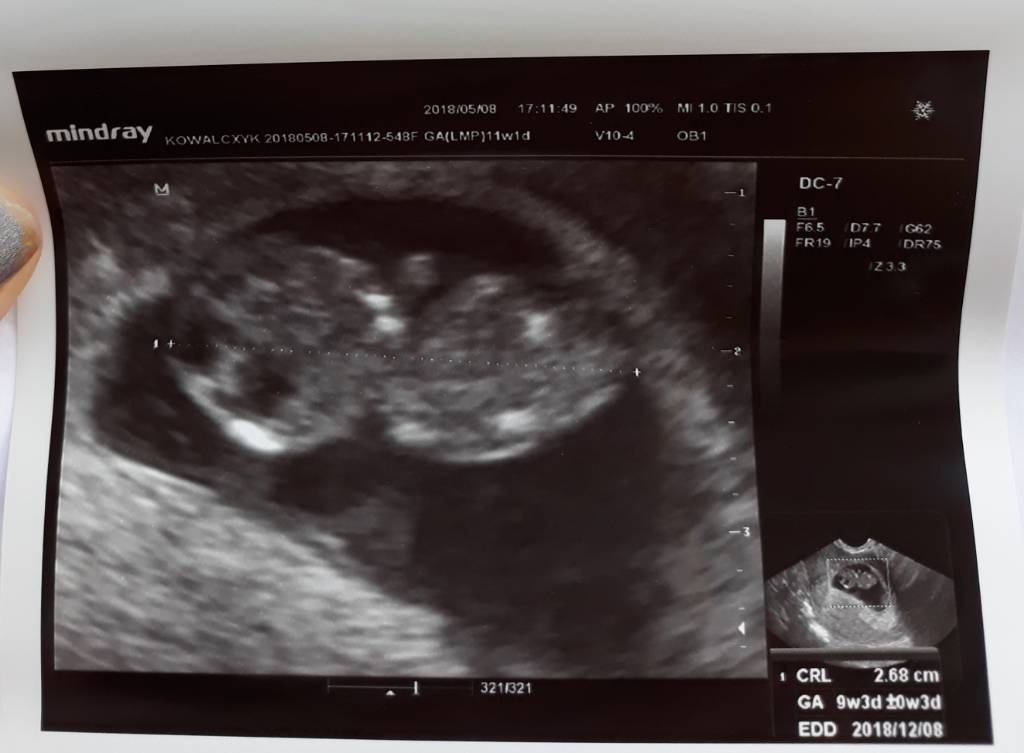

Chyba zostane z wami.Dzisiaj bylam na uzg kolejnym i jestem w 9t 3d ciazy to moja druga ciaza mam syna 10 lat [emoji16] na zdjeciu przyblizona date porodu mam 8 grudzien hehe zobaczymy jutro dopiero zakladam ksiazeczke ciazowa. A o to nasze drugie szczescie.

Zobacz załącznik 854872

Ja na om mam 11 t i 1 dzien wedlug ciazy 9 t i 3 d a porod mam na 8 grudnia niewiem czy dobrze jest. A i dziekuje [emoji6]